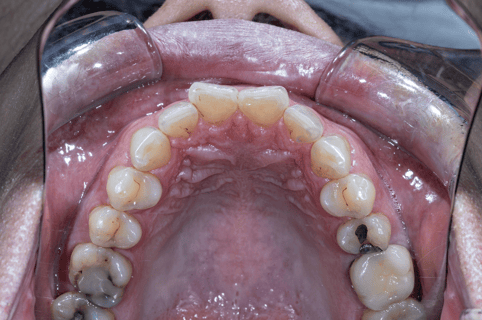

- 齒列排列不整,牙弓偏窄

- 咬合接觸不均,後牙支撐不足

- 下顎位置偏後,口咽空間受限

- 夜間磨牙,顯示咬合與肌肉代償